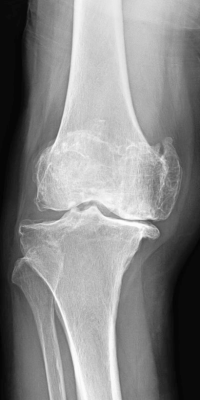

人工膝全置換術術前

当科で行っている主な手術は、骨折全般、変形性膝関節症に対する人工膝関節置換術(全置換、単顆置換)や高位脛骨骨切り術、膝半月板損傷に対する関節鏡手術、変形性股関節症に対する人工股関節置換術、神経・腱・血管に対する微小外科を含む手外科手術、肩腱板断裂に対する修復術、変形性肩関節症に対するリバース型人工肩関節置換術などです。

なお、人工膝関節置換術においては、症例に応じてナビゲーションの使用やオーダーメイド人工膝関節(PSI=Patient Specific Instrument)を用いた手術を行っております。また、人工股関節置換術においては、筋肉や腱の損傷を最小限にする低侵襲アプローチによる手術を行っております。